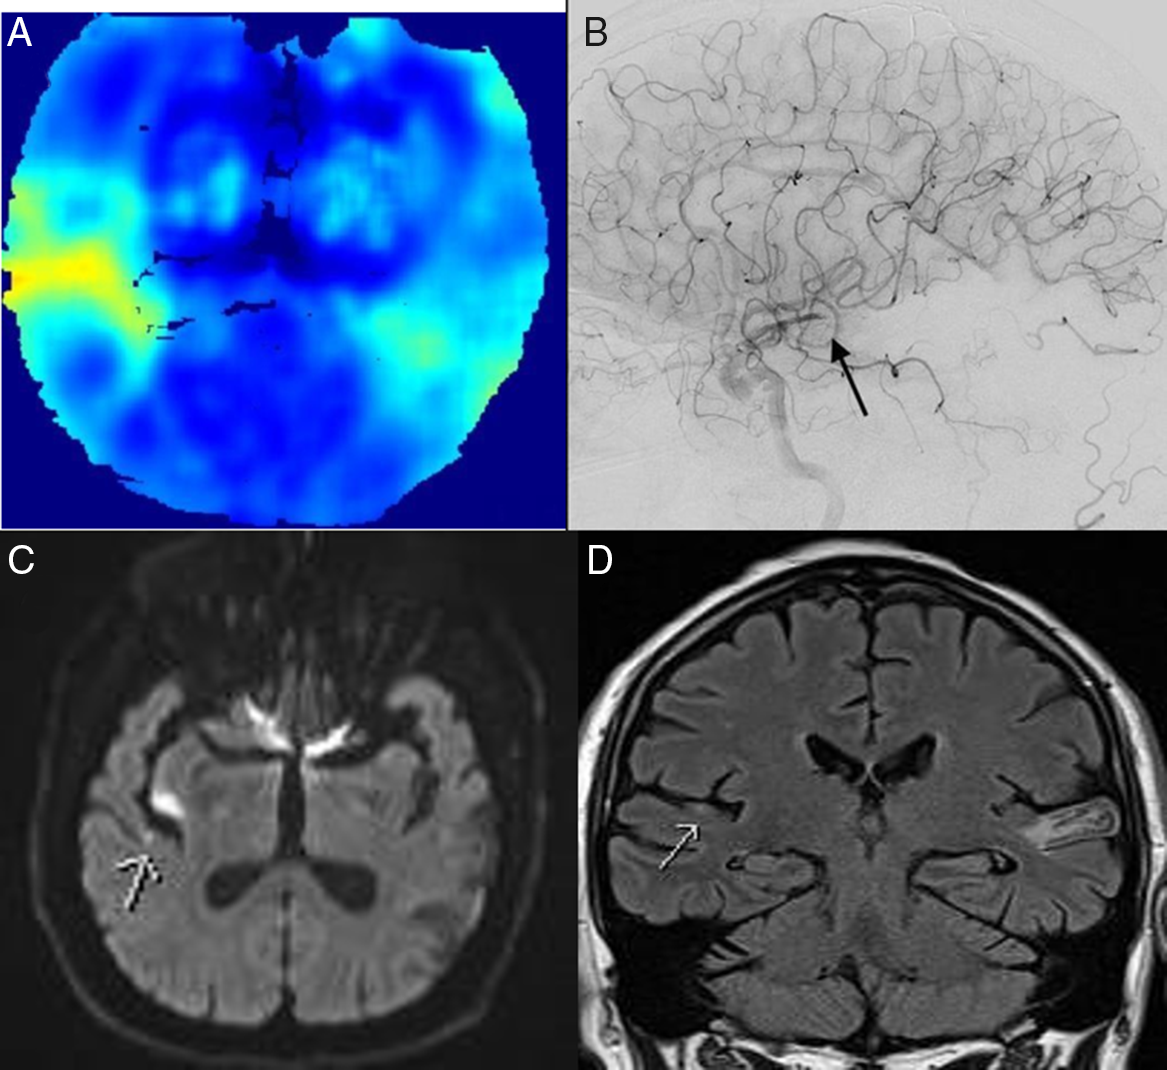

A 65-year-old man anticoagulated for atrial fibrillation and previous stroke presented with sudden deafness. Examination revealed normal fluent language, but he was deaf to intense sound. The computed tomography (CT) showed encephalomalacia in the left temporal lobe, and the multiphase CT angiogram revealed hypoperfusion in the superior right temporal lobe (Figure 1A) causing the acute deafness. Thrombectomy successfully recanalized the MCA branch occlusion (Figure 1B) with the return of the patient’s hearing. Magnetic resonance imaging (MRI) confirmed the acute infarct in the right Heschl’s gyrus (Figure 1C/D) and the chronic left transverse temporal gyrus infarct (Figure 1D). Sudden deafness is an uncommon, but treatable presentation of stroke. Reference Leussink, Andermann and Reiners1

Figure 1: CTA perfusion image (SPIRAL)Reference McDougall, Chan and Sachan2 showing right superior temporal lobe hypoperfusion (A). Right internal carotid catheter angiogram (B) demonstrating right posterior M3 branch occlusion. Diffusion weighted image (C) showing small right transverse temporal gyrus acute infarct following thrombectomy. Coronal FLAIR MRI (D) demonstrating acute right temporal and chronic left contralateral infarcts.